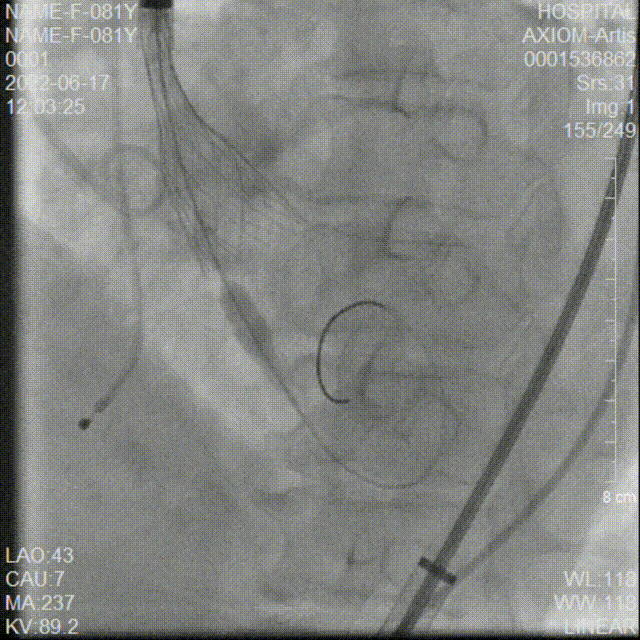

AV26瓣膜第四次释放到工作位

第四次释放到工作位造影检查

AV26瓣膜脱钩释放

AV26瓣膜完全释放后造影